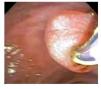

Variantes del ámpula de Vater (Figura 2):

¿ Figura 2. Variante anatómica del ámpula de Vater. Papila péndula: cuando los pliegues de la papila mayor obstruyen el conducto colédoco e impiden de forma importante su canulación directa, requiriendo la mayoría de las veces de precorte.

a. Papila péndula: cuando los pliegues de la papila mayor obstruyen el conducto colédoco e impiden de forma importante su canulación directa, requiriendo la mayoría de las veces de precorte.8